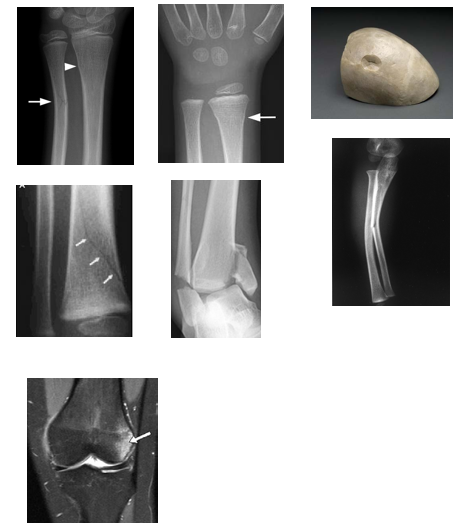

• Types of Fracture

–Incomplete

•Bow fracture (plastic deformation) – compression  bend to bone (juvenile) result of micro fractures

•Bone bruise (occult intraosseous fracture) – visible  radiographically – compression micro fractures

•Torus or buckling fracture –unilateral buckling of  cortex

•Greenstick fracture – incomplete transverse  fracture

•Toddler’s fracture – incomplete spiral or oblique  fracture

•Vertical fracture – fracture along long axis -  compressive

•Depressed fracture – inward pointing defect -  compressive

• Long Bone Blunt Force Trauma

•Blunt force trauma usually delivers  compressive and bending forces to long  bones

•Usually results in complete, simple  fractures without fracture lines

•Exception is greenstick fractures observed  in subadults

•Comminuted fractures can occur when  force is sufficient to shatter thick long  bone cortex

–  Butterfly fracture common in  car/pedestrian collisions

• Blunt Force Trauma to Other Bones

•Ribs

–Can break anywhere along body but prone to break at anterior ends

–Anterior or lateral blows

–Break at right angles to long axis when viewed externally

–When viewed superiorly or inferiorly they are observed to break from outside to inside